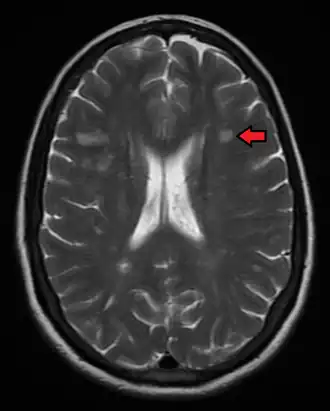

![]() МРТ-картина рассеянного склероза | |

- Магнитно-резонансная томография — метод визуализации мягких тканей, основанный на явлении ядерного магнитного резонанса. Он позволяет выявить очаги воспаления, но является ненадежным, потому что оценивает воспаление по косвенному признаку — изменению концентрации протонов. Которая может быть вызвана другими причинами[13]